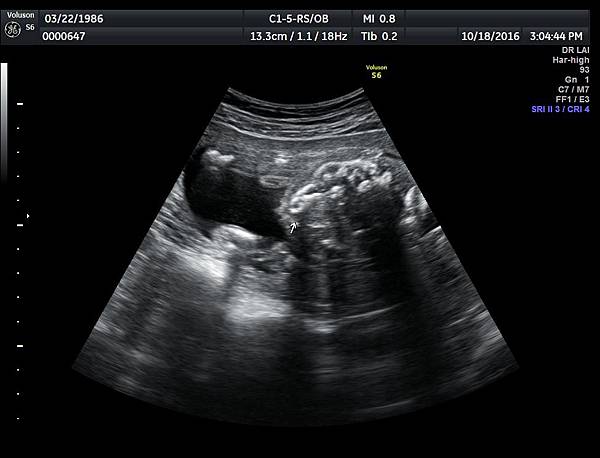

21w 6d right side cleft lip and palate and cleft uvula and brain anomaly < ACC and lissencephaly> images 3421

一個檢查如果要花很長的時間才能完成,這樣的檢查無法變成常規的篩檢方式,我已經在我的診所執行懸雍垂檢查一段時間,我檢查懸雍垂大約30 秒,前提是胎兒的臉最佳位置是側躺,其次是側躺偏向上,我的檢查步驟是上顎(含日後大門牙長出的位置)、舌頭、懸雍垂(= equal sign)(附圖1~8),如果超過60秒無法完成,只有兩個原因,一個是胎兒姿勢不適合或喉嚨羊水空間太小,這時候不要硬碰硬,只要先檢查其他部位,等待時機再回來即可,我的經驗是90%的cases都能順利完成這項檢查(肚皮厚的case真的是很難)。